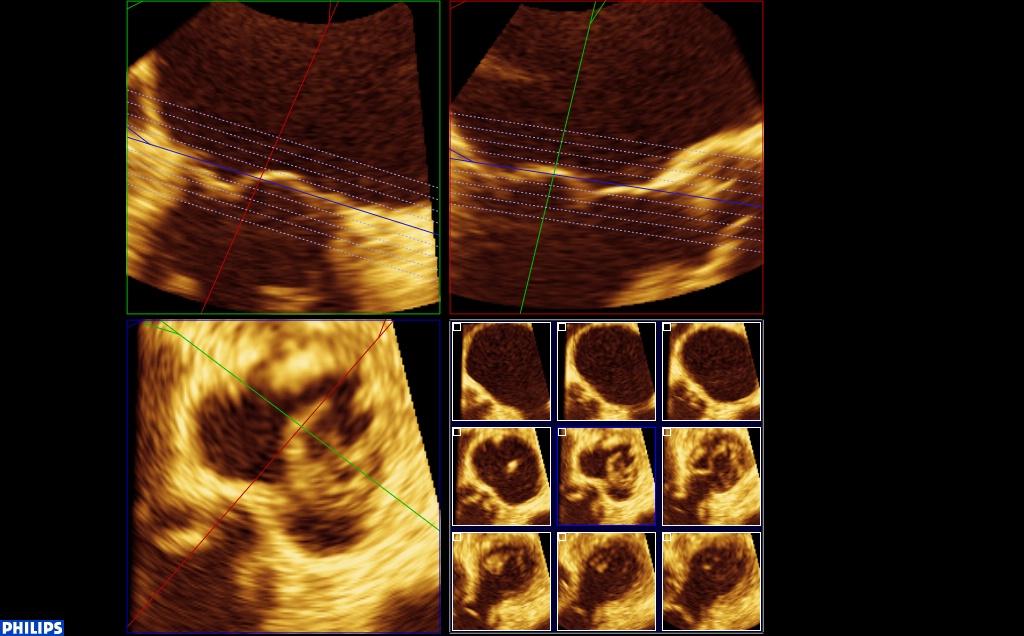

Vue 3D dite « chirurgicale », aorte en haut, auricule au gauche de l’écran, grande valve en haut avec un prolapsus médian et petite valve en bas :

Enfin, on note une dilatation et surtout une déformation importante de l’anneau (donc plutôt un type 1), qui est quasiment rond. Sur cette reconstruction tridimensionnelle de l’anneau en télésystole, les zones de restrictions paraissent en bleues, la zone prolabant (A2) est jaune. l’aorte est en haut, AL est la commissure antero-latérale.

Sur cette reconstruction 3D, on peut voir, dans le cadre en bas à droite, le petit carré bleu qui correspond au plan de l’anneau. Seul le A2 est au plan de l’anneau, le reste des feuillets sont en dessous, confirmant la restriction.